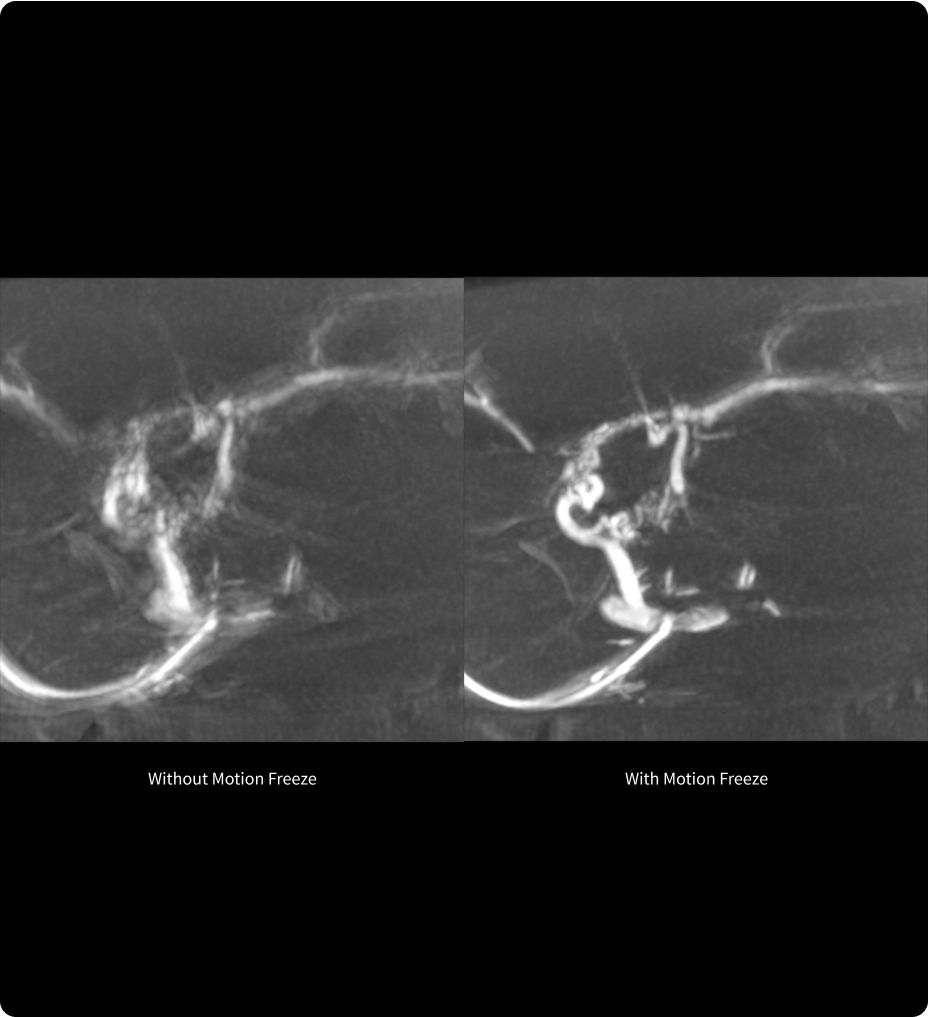

Motion Freeze6,7

Kompensierung von Atemartefakten, Minimierung der Strahlendosis

Motion Freeze ist eine bahnbrechende Lösung, die Bewegungsartefakte, die durch unwillkürliche Atembewegungen verursacht werden, deutlich reduziert und so die Klarheit und Genauigkeit von CBCT-Aufnahmen verbessert8. Es ermöglicht die Korrektur von Bewegungsartefakten in einem einzigen Scan, wodurch die Notwendigkeit von Wiederholungsscans verringert und so die Strahlenexposition und der Einsatz von Kontrastmitteln minimiert wird9.

Dank der Option zur schnellen Darstellung der Rekonstruktionsergebnisse optimiert Motion Freeze den Arbeitsablauf und ermöglicht die Wiederherstellung und Nutzung der ersten CBCT-Akquisition, die andernfalls möglicherweise verworfen worden wäre10.

6. Die mit Motion Freeze erzielte Verbesserung hängt von folgenden Faktoren ab: Aufnahmebedingungen, Tischposition, Patient, Art der Bewegungen, anatomische Lokalisierung und klinisches Verfahren.

7. Motion Freeze ist eine optionale Funktion von 3DXR (Bestandteil der vaskulären GE HealthCare Systeme IGS 5, IGS 6 und IGS 7 oder IGS 7OR). Motion Freeze und 3DXR werden möglicherweise nicht in allen Ländern angeboten. Nähere Informationen erhalten Sie von Ihrem Kundendienstmitarbeiter.

8. Mit Motion Freeze können kleine, kontrastarme Strukturen verfeinert und verstärkt werden. Auf diese Weise können CBCT-Aufnahmen nutzbar gemacht werden, die andernfalls aufgrund von Atembewegungsartefakten verworfen worden wären.

9. Motion Freeze kann dazu beitragen, wiederholte CBCT-Akquisitionen zu vermeiden. Dies verringert die Strahlendosis und die Kontrastmittelinjektionen.

10. Motion Freeze hilft, die Bilder aus der ersten CBCT-Akquisition zu nutzen, die normalerweise unbrauchbar wären. Dies ermöglicht den Einsatz von fortschrittlichen Lösungen.